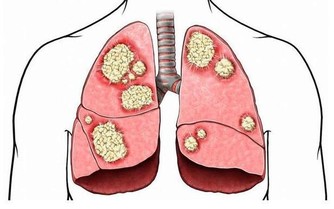

翻拍微信下同 其次當他入睡後依然維持了一個錯誤姿勢:側睡加頭低,導致頸部肌肉收緊,刺激了交感神經興奮,導致冠狀動脈平滑肌痙攣,心肌缺血,心梗而死。 頸椎病引起心臟病?是的! 專家說有可能!有一種心臟病就叫做頸源性心臟病,主要症狀包括如心前區作痛,心律失常,還會有胸悶不適感、心悸、氣促等。 看了下面數字,你怕不怕! 100個人中就有70個以上的頸椎病患者。 100個中風病症患者中有90%以上是由頸椎病引發的併發症。 100個腦癱病症患者中有63%以上是由頸椎病引發的併發症。 100個高位截癱病症者中有85%以上是由頸椎病引發的併發症。 100個猝倒死亡病症者中有95%以上是由頸椎病引發的併發症。 100個心肌梗塞病症者中有70%以上是由頸椎並引發的併發症。 100個腦血栓病症者中有80%以上是由頸椎並引發的併發症。 100個高血壓病症者中有60%以上是由頸椎並引發的併發症。 100個神經性胃潰瘍病症者中有75%以上是由頸椎並引發的併發症。 頸椎病有多要命?很危險! 更可怕的是,醫學上還發現頸椎病至少可引發全身70種病症,以下是幾種常見的病症。 1 吞咽不暢:吞咽時有梗阻感、食管內有異物感,少數人有噁心、嘔吐、聲音嘶啞、乾咳、胸悶等症狀。 2 視力障礙:視力下降、眼脹痛、怕光、流淚等,甚至還可能失明。 3 腹脹便秘:部分頸椎病患者因鄰近的頸交感神經受到刺激和損傷,使受其支配的內臟器官胃腸道蠕動減慢。 4 高血壓:血壓明顯升高,稱為「頸性高血壓」。由於頸椎病和高血壓皆為老年人的常見病,故二者常常並存。 5 胸痛:單側胸大肌和乳房疼痛,檢查時有胸大肌壓痛,這與頸六和頸七神經根受頸椎骨刺壓迫有關。 6 猝倒:站立或者走路時因突然扭頭出現身體失去支持力而猝倒,倒地後能很快清醒。 7 下肢癱瘓:早期表現為下肢麻木、疼痛、跛行,個別患者還有排便、排尿障礙,如尿頻、尿急或大小便失禁等。 8 老年痴呆:一旦頸椎間盤突出導致橫突孔變細、變形,會致使所供應的腦區發生供血不足,慢性腦缺血引起了遺忘等認知功能下降,長期以往最終會出現痴呆。 這頸椎病看著不起眼,可對我們的生命健康的威脅可是非常大! 奉勸頸椎不好的朋友千萬要當心,不要耽誤自己。在這裡提醒你,也希望你看到後提醒身邊的人:一定要關注自身的頸椎健康,別哪天被這頸椎病要了性命還不知道! 而很多人認為頸椎病不是很要緊的病,休息休息就好了,但是拖延下去,治療會越來越難,有的甚至要做手術治療,更嚴重的估計就會重演李建華的悲劇。所以勸大家及早預防,儘早治療! 脖子為什麼一轉就響? 因為我們身體的氣血供應不上,導致我們身體在變硬,關節在處於缺血狀態下的干磨。 氣血雙虧的身體相當於車軸里沒了油,很多人騎過自行車,知道如果車軸里缺油了,會感覺怎樣?一定是騎著費勁,一定會感覺裡面的滾珠轉動不靈活且有響動,有點類似我們的脖子響。只不過,自行車軸轉動靠的是油,而我們骨頭之間的轉動靠的是血液罷了。當我們血氣雙虧的時候,我們的骨關節之間的椎間盤,沒有充足的氣血供應,會形成干磨的情況,響動也就自然產生了。 骨關節為什麼會有病變? 1生理結構 人的頸椎和腰椎特別容易出問題,但胸椎卻好得多。這是因為我們的胸椎周圍有肋骨牽拉保護著,形成了一種力的相互作用,以確保我們的胸椎能夠保持中正。但是,頸椎和腰椎就不同了,它們沒有肋骨牽拉固定著,它們靠的是多組韌帶和小肌肉群。如果這些組織發生問題,就會導致我們的頸腰椎出問題。 2工作姿勢 當肌肉長期處於緊張狀態,就會感覺肌肉酸痛。正常情況下,如果胳膊腿酸了,我們活動一下,這樣的現象會很快消失,但是,用電腦就不一樣了,由於我們是長時間處於微弱的緊張狀態,這就好比溫水煮青蛙一樣,等我們查覺的時候,就已經晚了。它造成的後果就是,頸腰椎周圍的韌帶由於得不到充足的氣血供應,就會慢慢形成鈣化,兩側的牽拉受力開始不均勻,久而久之,椎間盤就會突出,擠壓周圍的組織和神經,頸腰椎病就會形成。 3工作環境 如果再加上工作環境的寒和濕比較嚴重,比如,在地下室工作、在空調底過的情況下工作,都會造成環境中的寒和濕進入到體內,特別是對於那些氣血本來就不夠通暢的肌肉和韌帶,會形成潛在的影響,加重了病變部位的病情。 4過食碳酸飲料 碳酸飲料會導致內脫鈣,久而久之,我們的骨頭變會得非常的疏鬆,那個時候,就不單純是骨頭響的問題了,而且還很容易導致骨折。 我們該如何調理? 下面介紹簡單易學的保護頸椎,甚至可以治好頸椎病的方法,大家一定要記好了! 1多多活動 天天以電腦為伴的朋友,用一會兒電腦,就要起來活動一下,同時活動一下脖子,但千萬不要做360度的圓周運動,只作90度向左轉,向90度的向右轉的動作,以確保我們脖子兩側的韌帶在短時間內,都能夠得到均衡的牽拉,以改善局部供血。而且切記動作要緩慢。 2不要讓頸部受涼 其是不要讓頸椎吹到冷風。頸椎受涼之後寒濕之氣很容易進入體內,而加重頸部韌帶的鈣化。 3杜絕碳酸飲料 減少包括可樂在內的一切碳酸飲料的攝入,因為這種溫水煮青蛙的過程是漸進的,因此很難被人們重視。 4打通經絡 這點最為重要。如果是脖子不舒服,最簡單的方法就是以自己的下巴寫米字,一天做一次即可,或在桌子邊擱後溪穴,以確保頸椎部的血液循環,使自己的頸椎摸著是溫暖的,而不是冰涼的。 5滾一滾、滾出好脊椎 站立歪斜或坐姿不端正、習慣性翹腳、長時間玩手機或者是坐在電腦前都會造成我們脊椎歪曲不直,脊椎一旦彎曲歪斜,很多毛病會跟著來。 中老年朋友可以常常做滾背的動作,矯正脊椎,甚至有人長了骨刺也可以治癒哦!每天勤快108下(來回一次算一下),骨刺免開刀,不用快慢慢做,矯正脊椎自己來! 滾背方式: 1、並腿屈膝坐在地上,兩手環抱住小腿,自然呼吸別太急促,收腹拱背,身體往後從尾椎、腰椎一節一節觸及地面,剛開始腳還先不用越過頭,多做幾下後再視自己身體狀況,然後滾到胸椎、頸椎,腳尖朝上,漸漸地雙腳越過頭,腳打直腳尖著地。